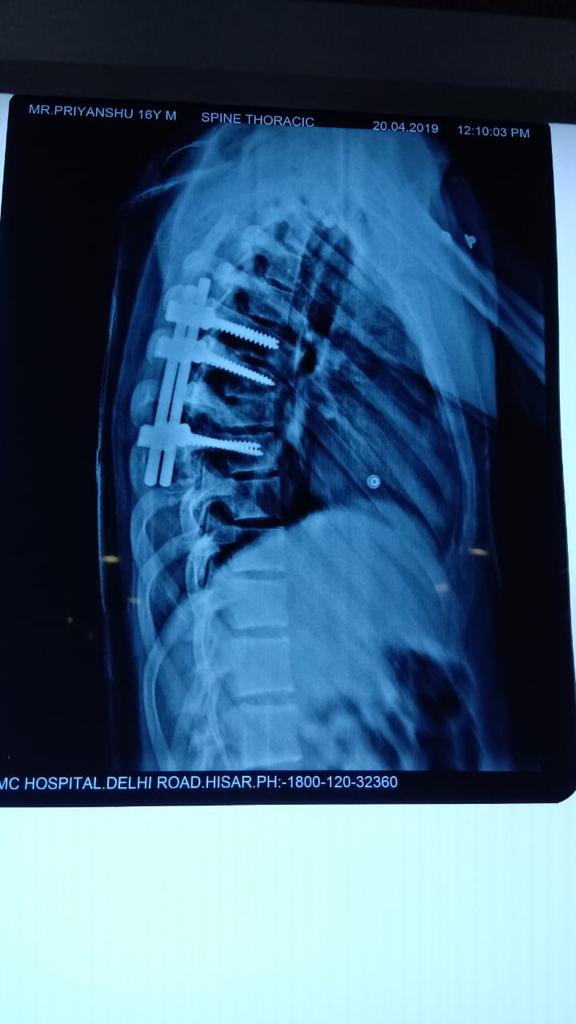

Cases